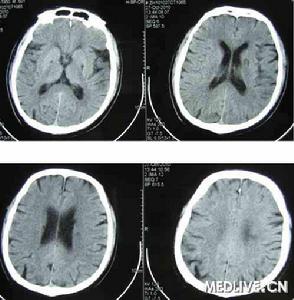

言語性失語屬經皮質運動性失語,對經皮質運動性失語負責的病變集中在兩個區域下後額區及上矢狀旁額區。當一急性病變如一次卒中累及上部運動前區時,可有完全性緘默或嚴重的發音困難多天,隨後能無聲說出字.繼之能低聲複述長的複雜的句子。輕偏癱累及腿比臂要重+面部及手不受累,感覺障礙不明顯,視野缺損少見,可有對側抓握反射及上肢肌強硬以及一過性尿失禁。可出現觀念運動性失用,大多影響非癱瘓的左上肢,後者自發活動正常,但接口頭命令進行活動卻很差。數日數周后發音困難常消失,1~2月內自發性言語明顯改善。病人不經歷音索性錯語或語法錯亂階段。